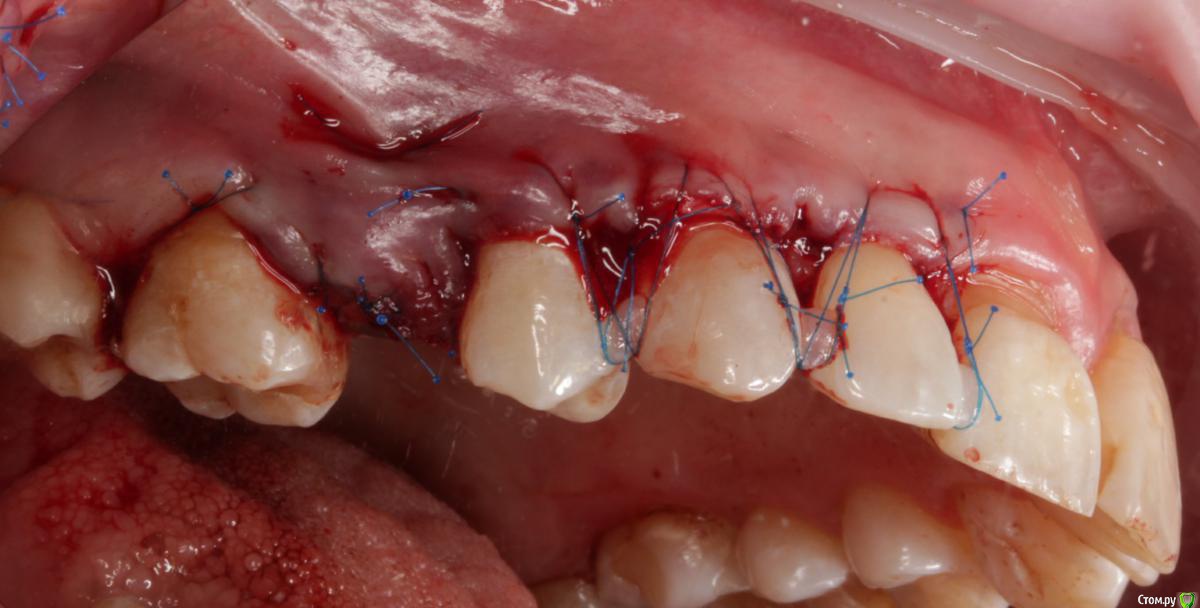

Dmitry DK Опубликовано 31 августа, 2019 Поделиться Опубликовано 31 августа, 2019 Доброго дня! Первичное обращение пациентки было связано с отсутствием 25 зуба, эстетические нарушения слизистой, клиновидные деф-ты в области других зубов - не смущали.В итоге решили, раз проводим операцию ( импл + ССТ ), закроем попутно и рец на верхней челюсти.Реставрацию на 21 зуб все не ставит... Приятных тебе выходных! ) Пациентка проходила лечение 2,5 года назад, пришла на проф осмотр 7 Ссылка на комментарий

Dman Опубликовано 2 сентября, 2019 Поделиться Опубликовано 2 сентября, 2019 ничего себе попутно, в итоге на имплант 15 минут, а на рецессии 2 часа?)) Ссылка на комментарий

Dmitry DK Опубликовано 2 сентября, 2019 Автор Поделиться Опубликовано 2 сентября, 2019 ничего себе попутно, в итоге на имплант 15 минут, а на рецессии 2 часа?))У меня те же мысли были), но согласитесь, что если бы мы этого не сделали - разница в зенитах былабы слишком велика Ссылка на комментарий